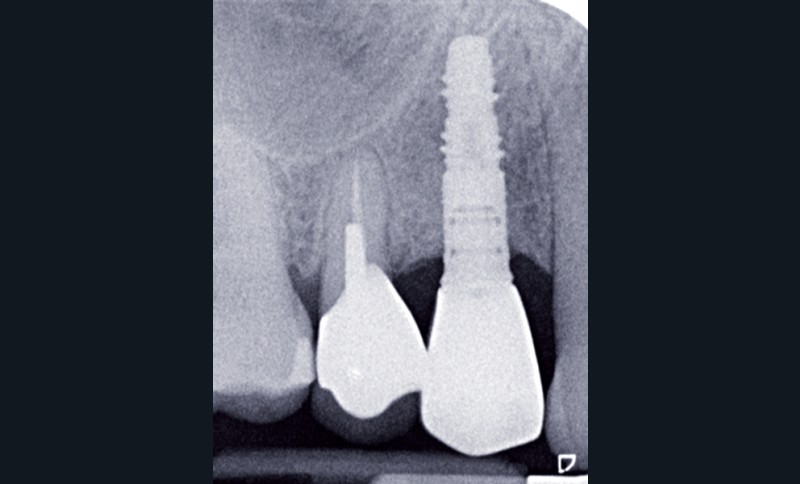

Le contrôle radiologique rétro-alvéolaire montre, quant à lui, une parfaite préservation de l’ostéointégration à 6 ans(fig. 3a et b).

Cette ostéointégration est confirmée par le Cone Beam(fig. 4a et b).